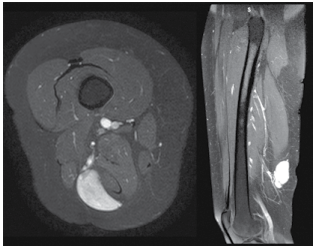

Uma paciente de 36 anos vem ao ambulatório de cirurgia vascular por apresentar nodulação em face posterior de coxa, depressível, pouco dolorosa e relacionada a ortostase. Como propedêutica complementar, a paciente já traz uma angioressonância com imagens de interesse apresentadas na figura a seguir:

(Arquivo pessoal; imagem usada com autorização)

A partir da análise das imagens, assinale a alternativa que corresponde ao diagnóstico em questão.